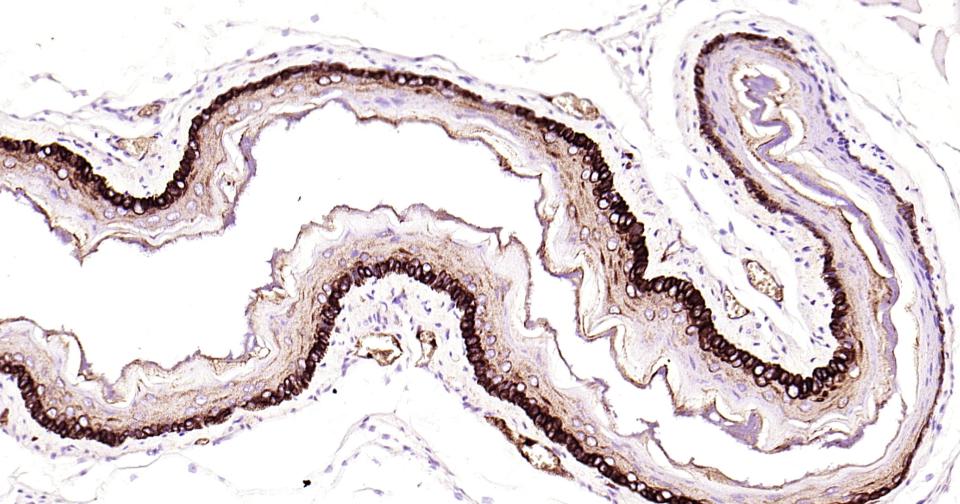

Paraformaldehyde-fixed, paraffin embedded Rat Esophagus; Antigen retrieval by boiling in sodium citrate buffer (pH6.0) for 15 min; Antibody incubation with Cytokeratin 14? Monoclonal Antibody, Unconjugated(bsm-52054R) at 1:200 overnight at 4°C, followed by conjugation to the bs-0295G-HRP and DAB (C-0010) staining.